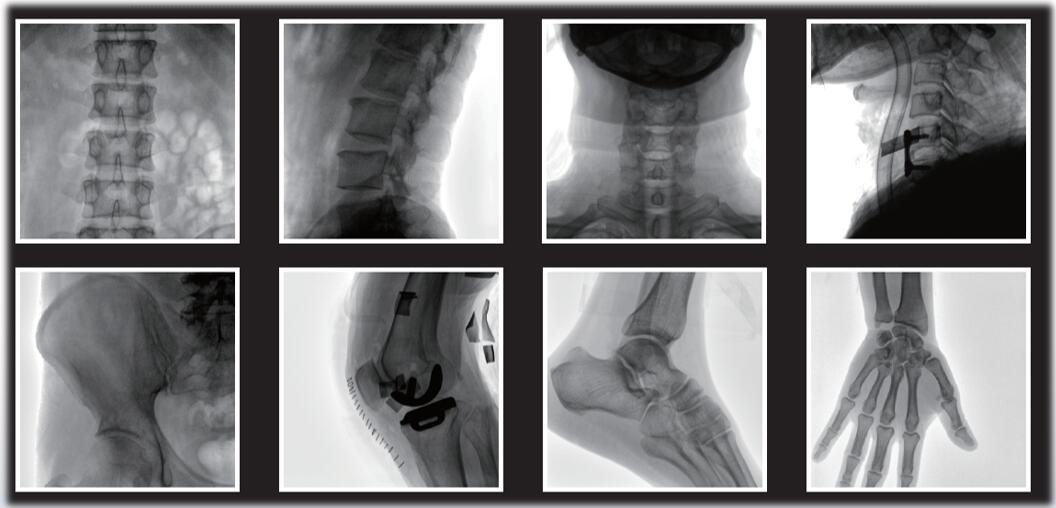

平板小C臂臨床影像

平板小C臂在骨科手術中的定位、診斷、微創手術的開展與治療中發揮獨特的作用。作為一名醫生,您需要清晰的圖像質量來幫助您應對更具挑戰性的介入治療。PLX118系列平板小C臂為您提供優良的圖像、靈活的操作體驗和更低的劑量表現。如果您想采購,或了解產品具體參數,歡迎咨詢400-025-6366